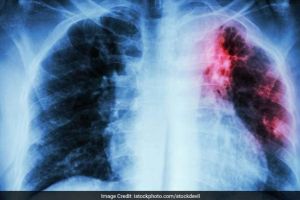

Ion Iliescu, în stare critică avansată la spital. Diagnosticul stabilit de medici: pericardită hemoragică

Ion Iliescu a ajuns ieri, de urgenţă, la spital. Fostului lider de la Cotroceni i s-a făcut rău, luni, în jurul orelor prânzului....

Institutul de Boli Cardiovasculare: Ion Iliescu a fost operat; este stabil si in afara unui pericol iminent

Fostul presedinte Ion Iliescu a fost supus luni unei interventii chirurgicale cu un rezultat final foarte bun, informeaza Institutul de Urgenta pentru Boli Cardiovasculare "Prof. C.C. Iliescu", inform

Fostul preşedinte Ion Iliescu, operat de urgenţă – Medicii vin cu detalii

Fostul şef al statului a fost internat luni de urgenţă la Spitalul Elias din Capitală. Ion Iliescu a fost operat de medici şi se pare că se simte bine. Ion Iliescu a fost operat de medicii de la Institutul C.C. Iliescu, diagnosticul său fiind pericardită lichidiană - tamponadă cardiacă. Conform…

Fostul presedinte Ion Iliescu a fost supus unei interventii chirurgicale. In ce stare este fostul sef de stat

Fostul presedinte Ion Iliescu a fost supus luni unei interventii chirurgicale cu un rezultat final foarte bun, informeaza Institutul de Urgenta pentru Boli Cardiovasculare Prof. C.C. Iliescu citat de ...

Breaking News! Informaţie de ultimă oră despre Ion Iliescu

Ion Iliescu se află în afara oricărui pericol potrivit unui comunicat de presă emis de Institutul de Boli Cardiovasculare „Prof. Dr. C.C. Iliescu”, unde a f...

Anunţ de ultimă oră! Ion Iliescu la terapie intensivă

Deşi medicii de la Spitalul Elias au transmis că Ion Iliescu s-a prezentat la un control periodic şi că starea lui nu este una gravă, surse ale Realitatea T...

Fostul presedinte Ion Iliescu a fost internat in spital. Cu ce probleme medicale de confrunta fostul sef de stat

Fostul presedinte Ion Iliescu a fost internat, luni, la Institutul de Urgenta pentru Boli Cardiovasculare Prof. C.C. Iliescu din Capitala pentru investigatii amanuntite la inima, au confirmat pentru ...